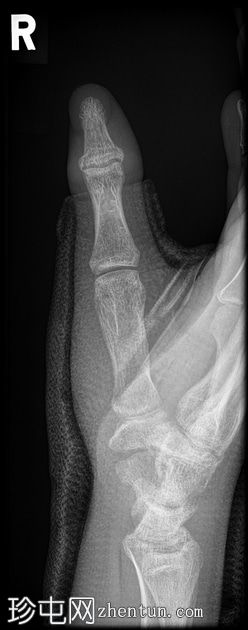

侧位片

玻璃纤维拇指人字形石膏固定。

舟骨腰部骨折合并骨折。

第一近节指骨背侧基底部急性关节内骨折。

这位患者很不幸——舟骨骨折几乎已经痊愈,却因摔倒导致拇指远端指骨再次骨折。当然,拇指人字形石膏固定并没有起到作用,反而可能由于近节关节活动范围减小而导致撕脱性骨折。